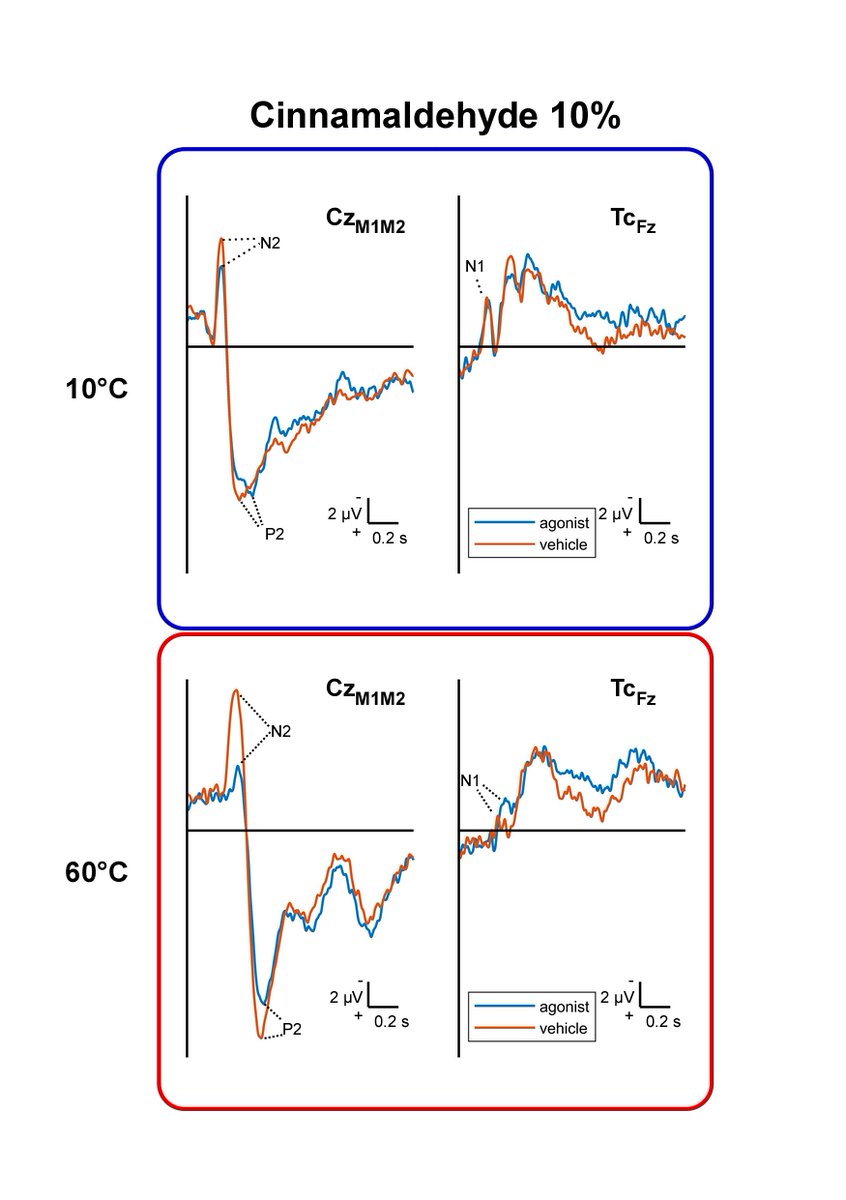

"Combining Topical Agonists With the Recording of Event-Related Brain Potentials to Probe the Functional Involvement of TRPM8, TRPA1 and TRPV1 in Heat and Cold Transduction in the Human Skin", by @arthur_courtin and André Mouraux is now out! sciencedirect.com/science/articl…